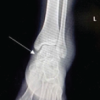

A 42-year-old housewife came to the orthopedic outpatient department with complaints of insidious onset dull pain and mild generalized ankle swelling in the right ankle for 2 years. On examination, there were no skin changes over the swelling and ankle range of motion was complete without any pain. She was given treatment in the-form of analgesics which failed to relieve her symptoms. She was referred for further evaluation to our center. Radiographic examination showed a lytic lesion in the talus with a narrow transition zone and irregular calcifications at the center (Figs. 1a and b).